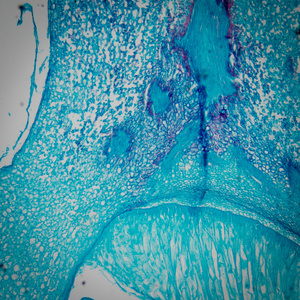

箭头所示为玉米胚芽

图片尺寸741x702